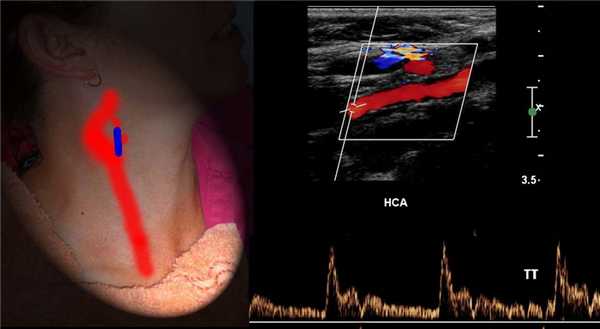

У основания шеи кнутри от ОСА щитовидная железа, кнаружи — внутренняя яремная вена. Под давлением датчика ВЯВ сжимается, а ОСА нет.

От основания шеи перемещайте датчик вверх к бифуркации ОСА — место деления на НСА и ВСА. Здесь небольшое расширение — луковица.

У бифуркации ОСА расширение луковицы, начинается голый ствол ВСА и ветвящаяся НСА. Первая ветвь НСА — верхняя щитовидная артерия.

На уровне бифуркации ВСА шире НСА; расположена кнаружи и кзади от НСА, выше перемещается кнутри; не имеет ветвей на шее.

В луковице ламинарный поток по основной оси ВСА красный, а зона турбулентного потока у наружной стенки окрашивается в синий.

Спектр ОСА имеет резкий подъем и узкий пик в систолу, низкий поток в диастолу, дикротический вырез в поздней систоле и ранней диастоле.

Cпектр НСА похож на ОСА, иногда ретроградный поток в диастолу, звук «стреляющий». Постучите по поверхностной височной артерии, увидите Т-волны на спектре НСА.

Спектр ВСА имеет постепенный подъем и широкий пик в систолу, высокий антеградный поток в диастолу, пульсация почти отсутствует, звук «дующий».